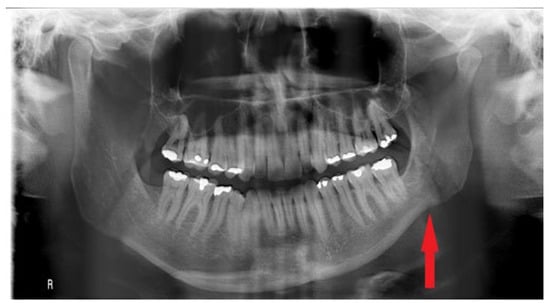

O—open bite at the canine, premolar area (Figure 2)—visible in RTG as the enlarged distance from upper and lower dentition on the HH side;-greatly related to individual factors especially the degree and occurrence time of pathological growth;

Figure 2. Visible open bite and increased vertical distance between upper and lower anterior teeth.